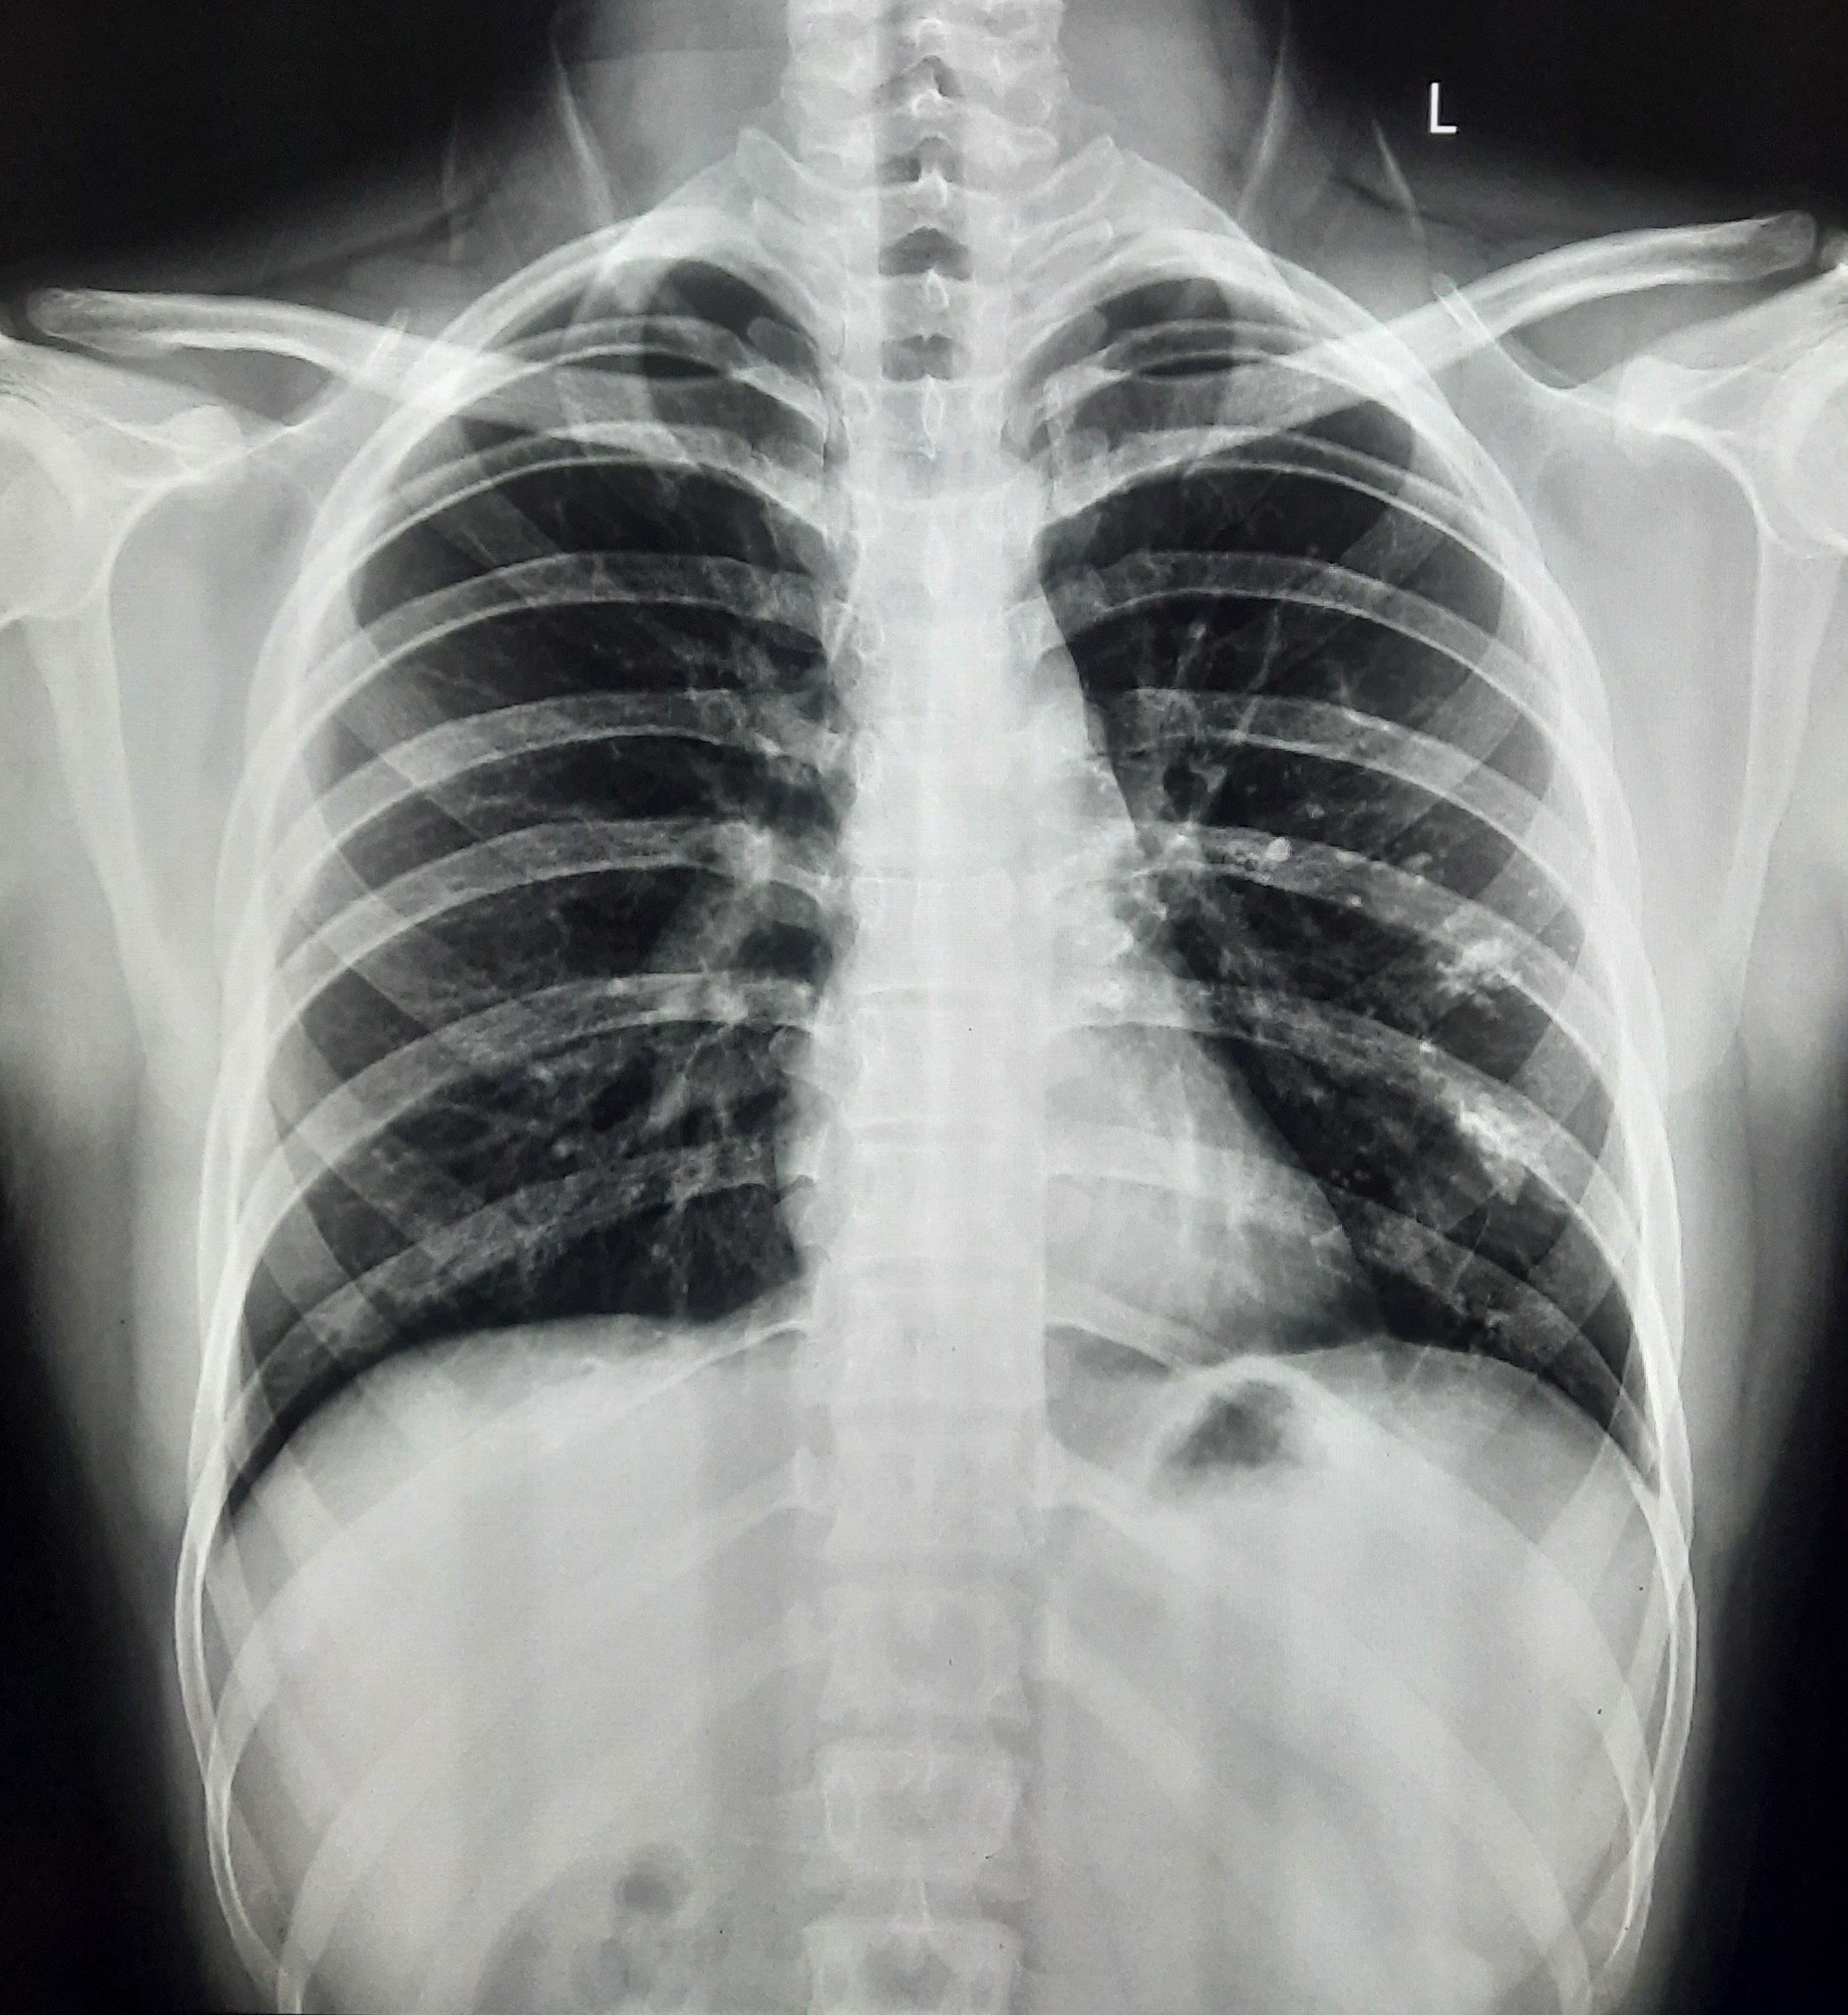

| 137 | IGGMC, Nagpur, Nagpur | P2 | 29-4335 | Naresh Markam | Consent taken on Paper | 52 Yrs. |

Provisional Diag : PTB?

Final Diag : Pulmonary Tuberculosis ( Microbiologically Confirmed PTB) |

TB Case (Confirmed) | Bilateral Upper Zone Infiltration With Middle Zone/ Lower Zone Infiltration | Abnormality visible on x-ray |